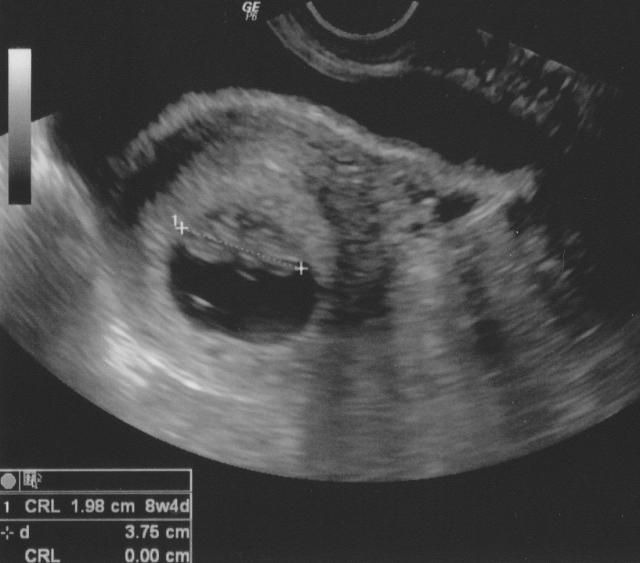

Tänään kävimme (Femedassa) varhaisraskauden ultrassa, siellä se pieni sydän pamppaili (syke 180). Henkilökohtaisesti koen, että raskaus muuttui kohdallani vieläkin konkreettisemmaksi, kun pääsi näkemään pienen elämänalun. Kokoa pienellä oli 23mm, ja viikot 9+0 LA vahvistui 15.12.2014.

Noniin, nyt on sitten takana neuvolan ylimääräinen ultra, joka on jo toinen tässä raskaudessa. Ensimmäinen tehtiin 6+4 päivystyksessä kirkkaan verisen vuodon takia ja tämä oli sitten neuvolalääkärin tekemä noiden samojen vuotojen takia, jotka ovat jatkuneet koko alkuraskauden. Syke löytyi heti ja oli kuulemma vahva. Samaten koko vastasi lähestulkoon viikkoja - 8+4 oli lääkäri arvio koon mukaan, joka heittää parilla päivällä alaspäin kuukautisista laskettua raskauden kestoa. Kokoa kippuralla oli 2cm. Vuotojen syytä ei varmuudella selvinnyt, mutta lääkäri arveli istukan reunan vuotavan, sillä on melko alhaalla ja hyvin lähellä kohdun suuta. Kohdun suu on tiukasti kiinni, joten vuoto tuskin tulee sieltä. Hematoomia ei näkynyt, eikä mitään muutakaan selvää merkkiä vuodosta. Vuoto onkin ollut melko niukkaa tässä viimeaikoina. Jos vuoto lisääntyy tai tulee kirkasta verta (tullut kahdesti tähän mennessä) täytyy mennä tarkistuttamaan asia, mutta riittää, kun käy lähipäivinä. Ultratessa löytyi myös kysta oikealta munasarjoista, mutta on kooltaan vain parisenttinen, eikä siitä tarvitse lääkärin mukaan huolestua. Käski unohtaa koko asian.. :)

Ihana asia tosin oli, että lääkäri ymmärsi hyvin ahdistuksen ja pelon siitä, että entä jos kaikki ei olekaan hyvin. Hän sanoikin, että nyt ultran jälkeen kaikki on hyvin ja on helppo olla luottavaisin mielin, mutta kotona helposti jää miettimään, onko kaikki edelleen hyvin. Saan kuulemma soittaa aina tarvittaessa ja ultraavat, jos minulla on sellainen olo, että asia mietityttää. Lääkäri siis puhui tästä ihan itse, enkä edes ehtinyt puhua omasta ahdistuksestani tai pelostani mitään. Otan asian kyllä puheeksi ylihuomenna neuvolassa. Mutta hyvä tietää, että ottavat melko helpostikin ultraan, jos siltä tuntuu. Johtuuko sitten vuodosta vai mistä. Lääkärin mukaan vuoto tuskin on haitallista, kun sitä on ollut jo näin pitkään ja kaikesta huolimatta raskaus on edennyt normaalisti. Saatiinpa mukaan yksi kuvakin.. :Heartred

1352014.jpg

Tänään varhaisultrassa. Piti olla viikkoja 7+4, mutta kokoa kaverilla olikin vain 7,7mm joten vastaa lähemmäs 7+0. Sydän siellä lujasti pamppaili...oih :Heartred Mielenrauha on saavutettu joten ehkä sitä saapi jo yötkin nukkuttua kunnolla ;) Mahtava fiilis o kyllä!